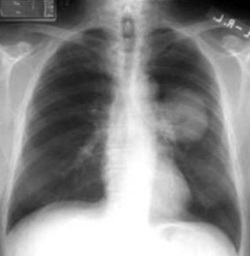

15

Q

¿Cuál es el dx?

A

Neumotórax